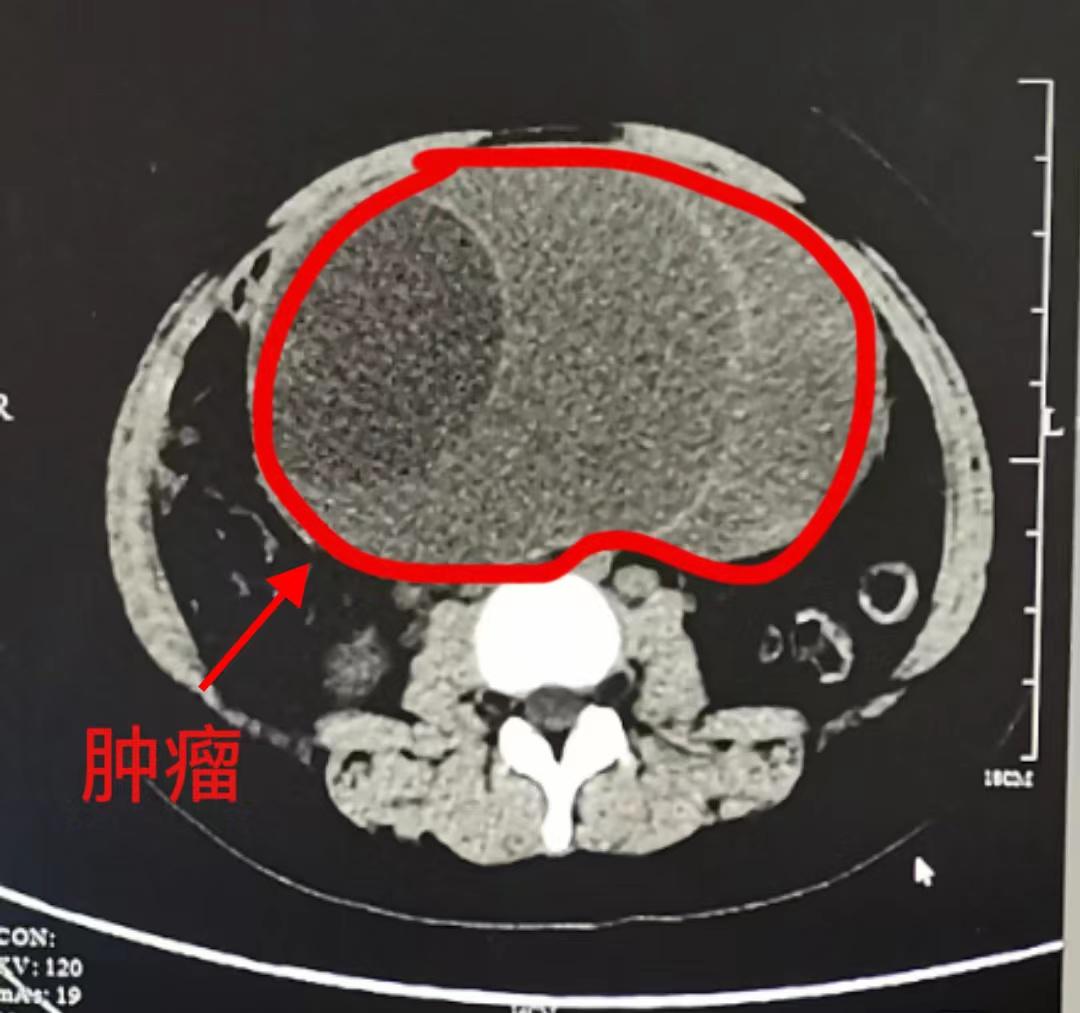

肚子莫名变大都是在偷偷“发福”吗?今天,我们的故事便发生在15岁的小张和她鼓囊囊的肚子上面。三年前,小张经常运动后下腹不舒服,肚子也开始渐渐“长大”,检查B超提示附......